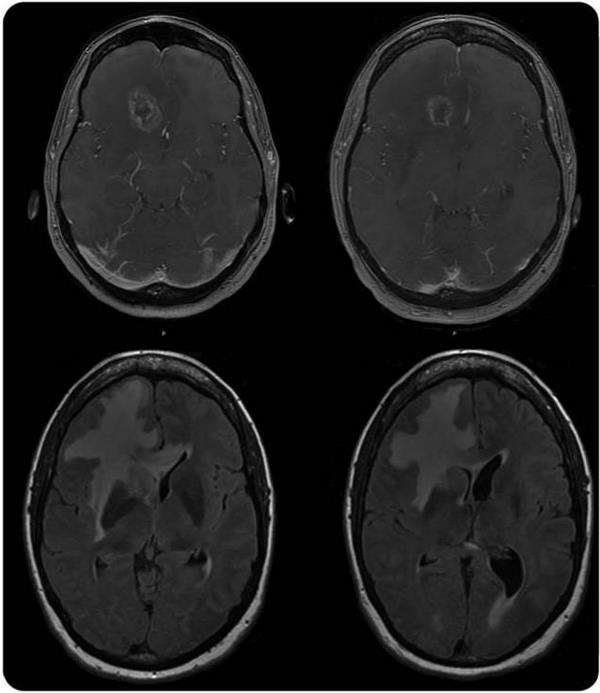

患者女性,44 岁,有视网膜血管病变的病史,主要症状为头痛和轻偏瘫。MRI 大脑显示右额叶周边有高信号的肿块且其周围水肿 (如图 1),考虑为恶性神经胶质瘤。然而,病理显示为反应性胶质增生坏死,没有证据提示是肿瘤 (如图 2)。家族中多个亲戚的头部 MRI 显著相似的可疑肿瘤病变,但是组织活检排除肿瘤。怀疑为潜在的家族性脑白质病,异常的杂合无义突变在 TREX1 基因的 c.1359 G> T;p.Glu285 * 被确认,C 端的移码突变导致常染色体显性遗传视网膜血管病变伴有大脑白质脑病。

图 1 2008 年的头颅 MRI:右额叶边界不规则的高信号肿块伴广泛血管性水肿

图 2 2008~2014 年 6 年的核磁共振系列成像显示增加支流 FLAIR 在前额和右室周旁白质高信号